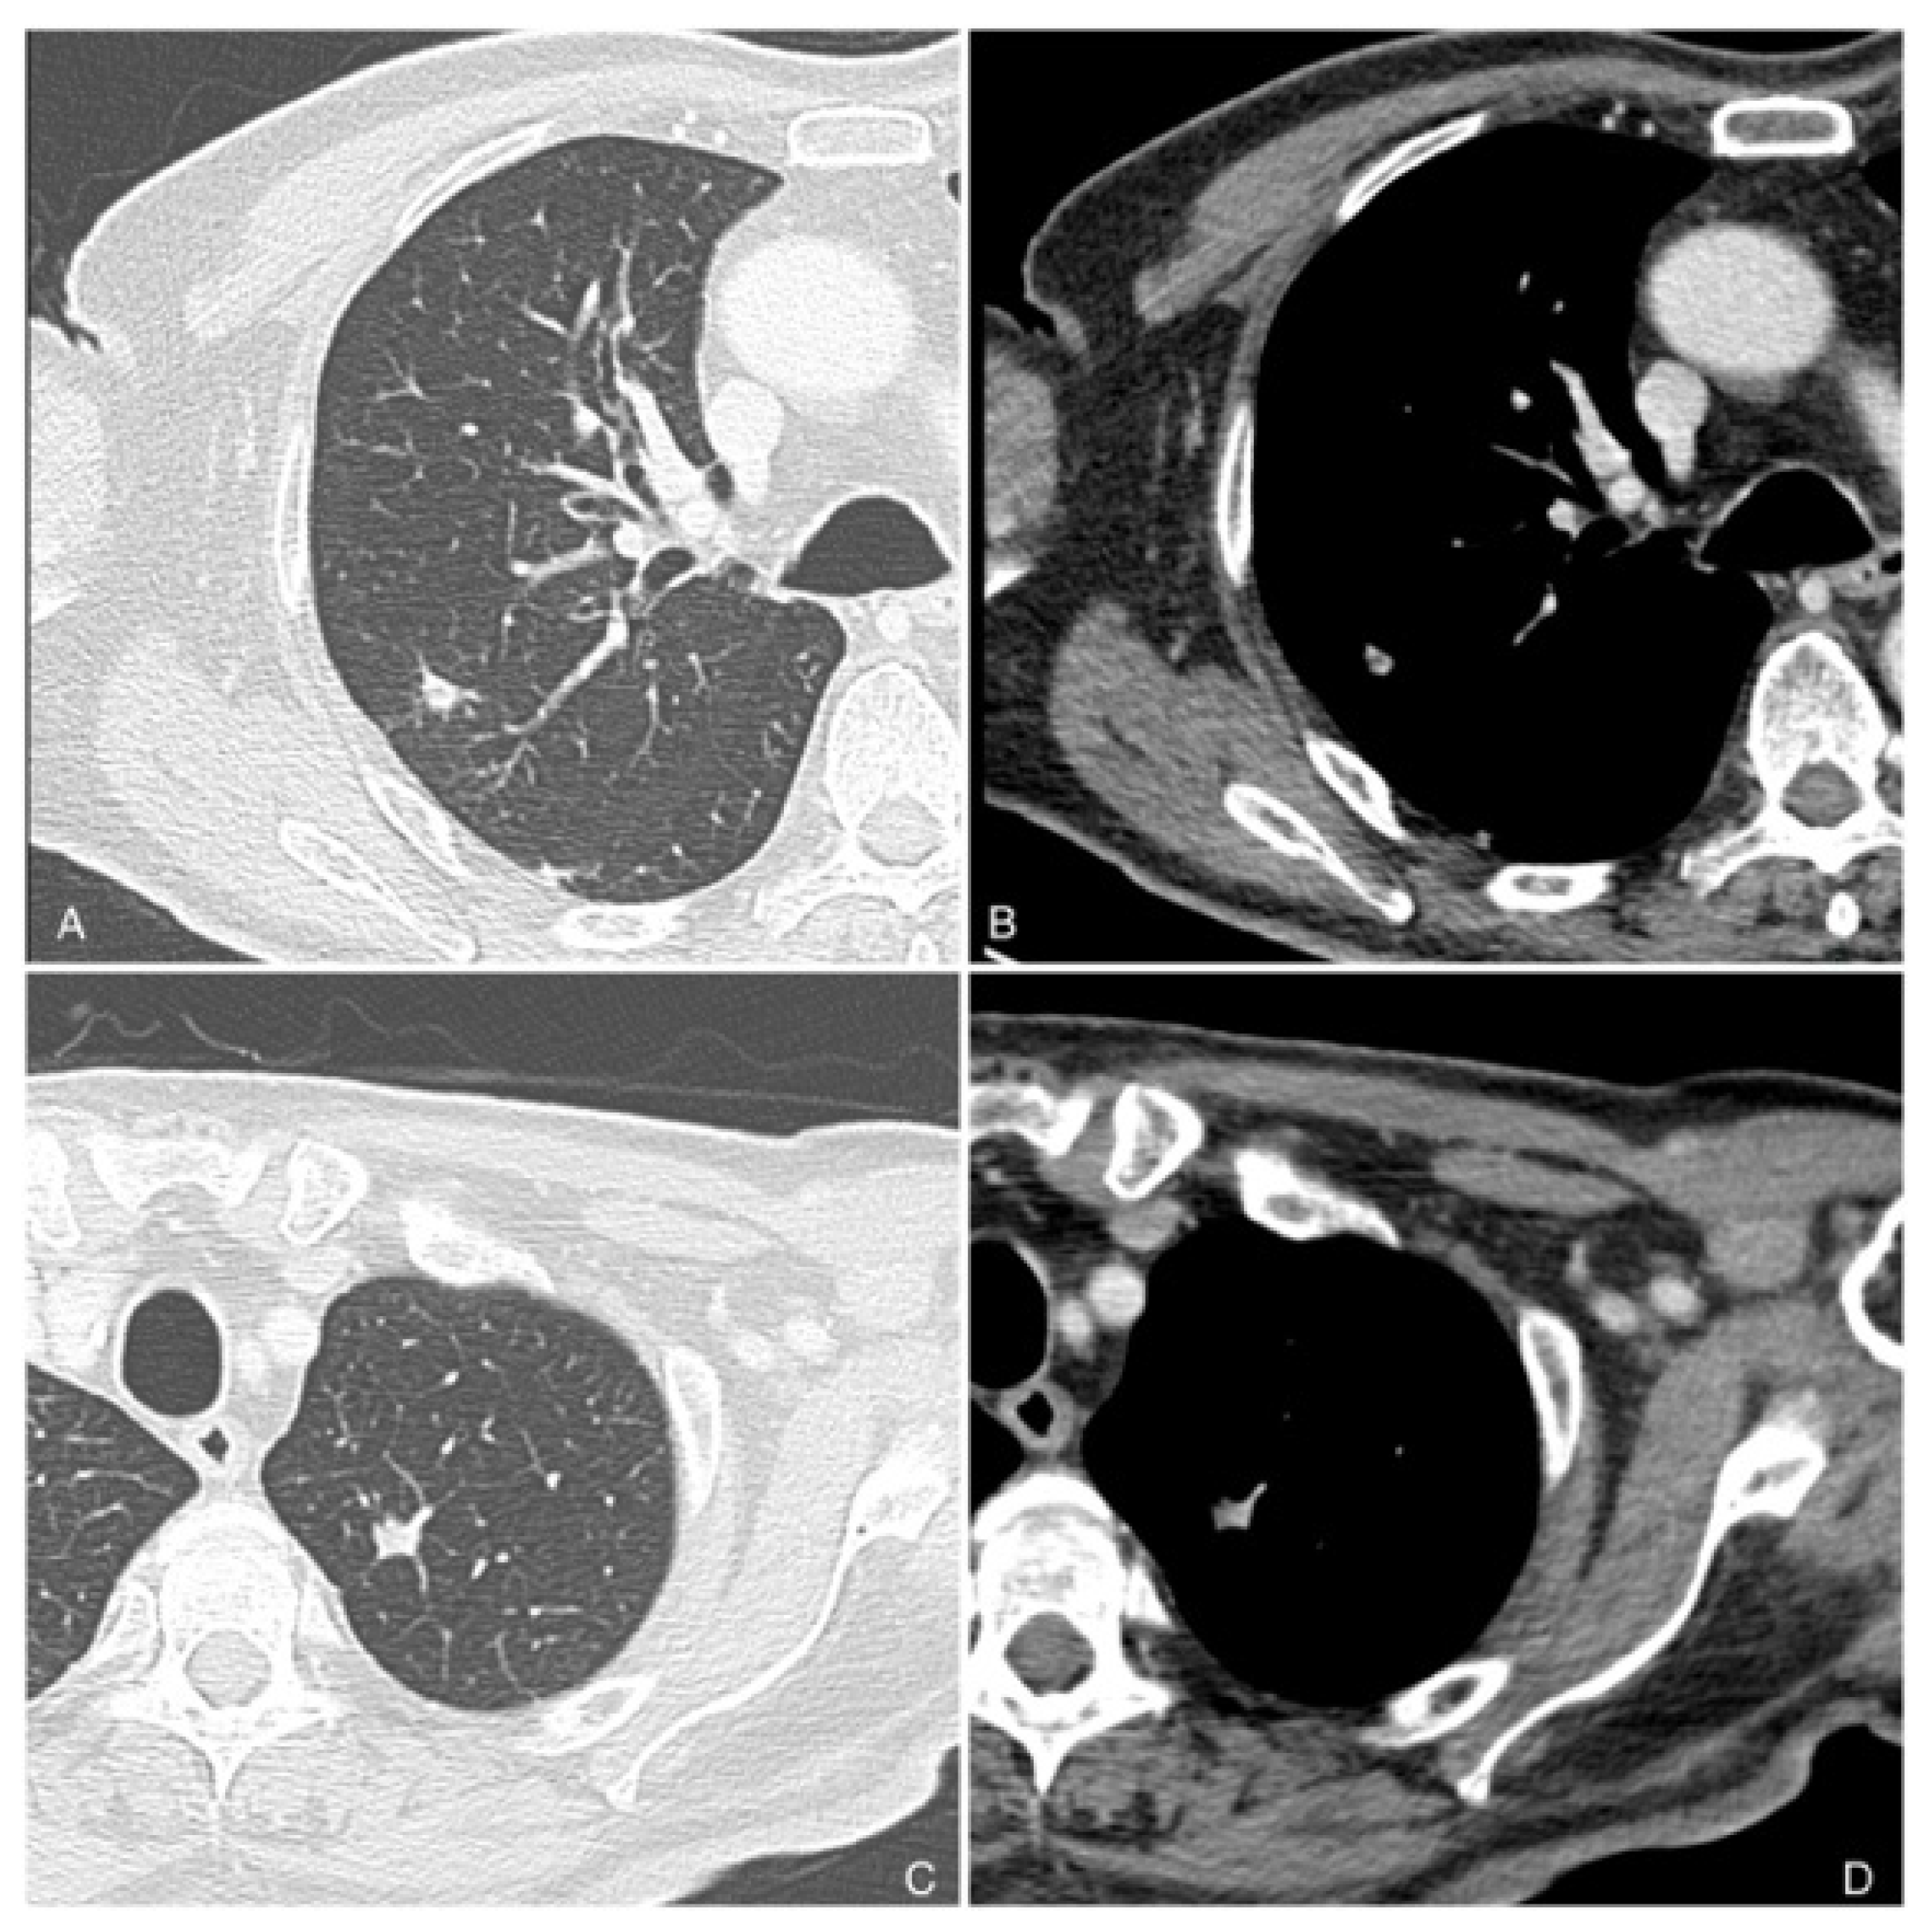

7. The Role of Imaging in Cutaneous Squamous Cell Carcinoma

7.1. CTA Protocol

8. Follow-Up Imaging